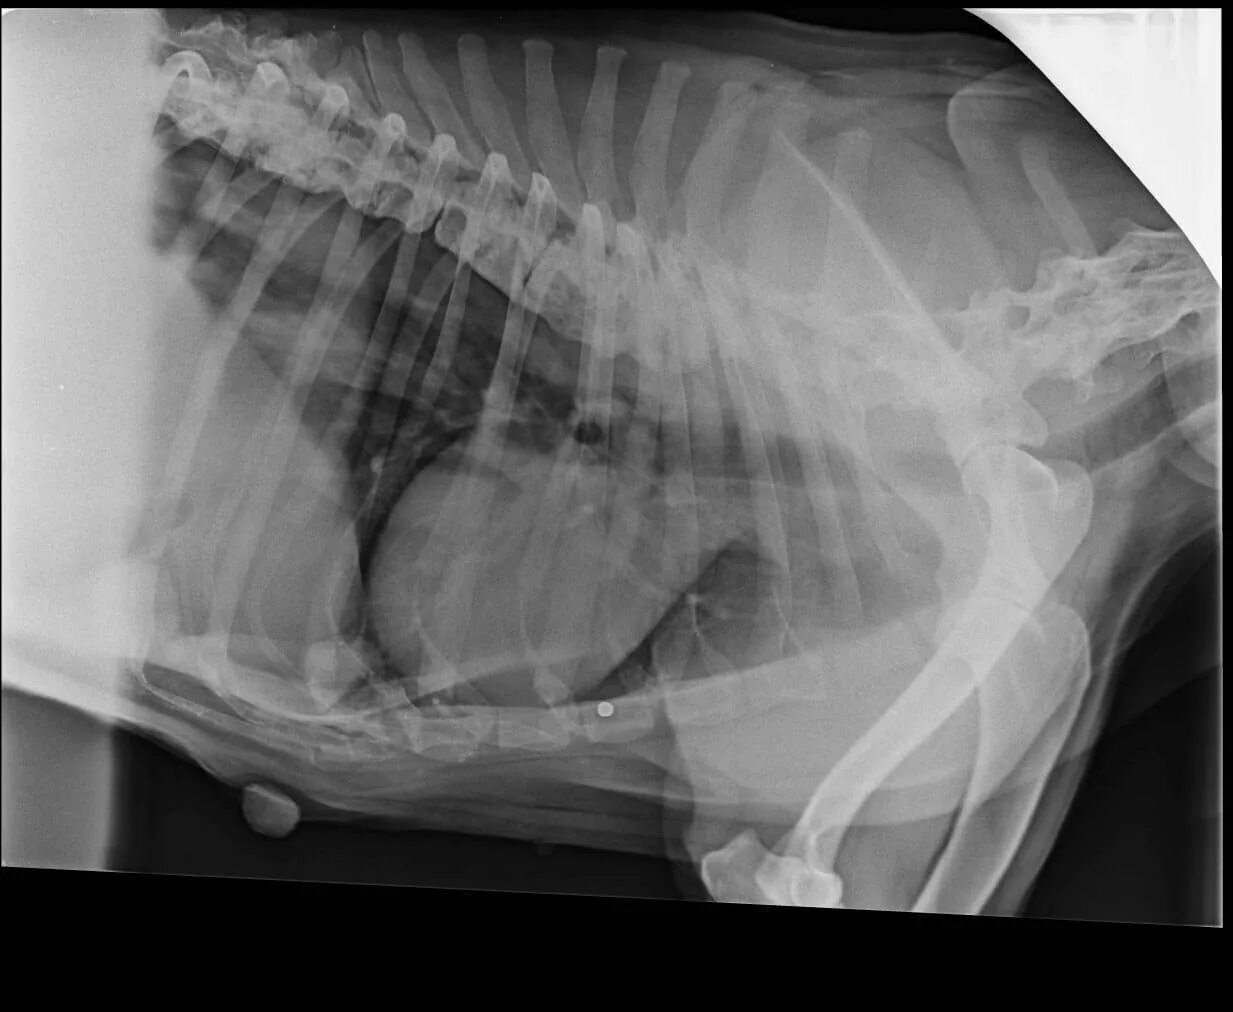

Делала рентген при беременности